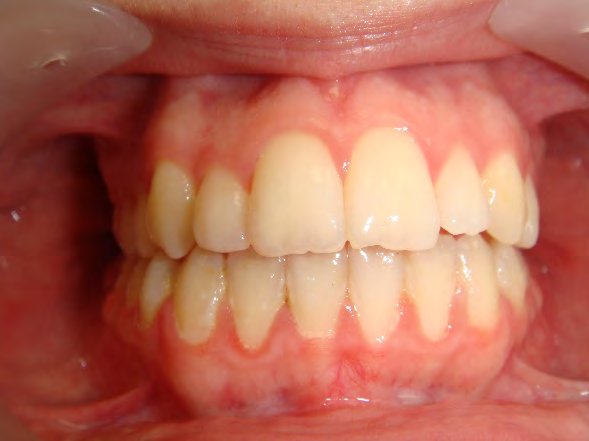

All of the patients below had been told they required extractions by orthodontists, some insisting that they could not be treated without extractions.

They were all treated without extractions, head gear or facemasks at Vakresmil and represent just a small sample of cases treated between 2004–2014.

Below are cases treated at Vakresmil without extractions within the last three years. The families had been told, “It is simply not possible for your child to be treated without extractions” by orthodontists. Judge for yourself if that was right or wrong.

The overall aim is to produce the best smile we can — a “beautiful smile”, if you will — without premolar extractions, headgear, facemasks or banded appliances. A smile that both the patient and we at Vakresmil can be proud of.